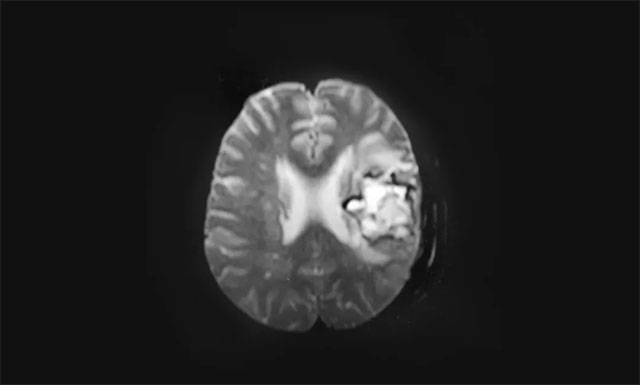

▲ 术后影像显示左侧额骨骨质不连续,毗邻皮下软组织稍肿胀,呈术后改变